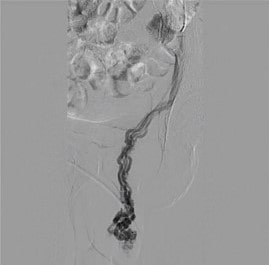

Из специальных инструментальных исследований обязательно УЗИ с УЗИ Допплер. Во время ультразвукового исследования мошонки можно определить расширенные варикозные узлы семенного канатика. Опытный специалист обнаруживает рефлюкс из почки по яичковой вене. При осмотре артерий брюшной полости обнаруживаются аорто-брыжеечные щипцы и увеличение почечной вены. Хорошая ультразвуковая диагностика позволяет с большой уверенностью установить диагноз и причину варикозного расширения вен семенного канатика. Окончательный диагноз и выбор метода лечения варикоцеле осуществляется с помощью флебографических исследований (ретроградная почечно-яичковая флебография, антероградная флебография). Эти методы диагностики позволяют судить о состоянии функции яичковой вены, выявить патологическое отхождение крови из левой почки в мошонку и определить степень варикозной трансформации ациниформного сплетения. Флебография включает пункцию основной вены на ноге или шее с последующим введением катетера в левую почечную вену и введением контрастного вещества, непрозрачного для рентгеновских лучей. Пациента просят глубоко вдохнуть, чтобы оценить, как контраст распространяется от почечная вена к яичку. С помощью флебографии можно оценить диаметр яичковой вены и вен гроздевидного сплетения яичка. Учитывая, что это исследование инвазивное и проводится через пункцию, мы проводим его во время эндоваскулярного лечения, которое следует сразу после постановки диагноза — окклюзии тестикулярной вены с помощью специальных спиралей или эмболов.

Яремная или бедренная вена под контролем УЗИ катетеризуется по Сельдингеру, катетер вводится в яичниковую вену и вводится специальный эмболизирующий агент. Наши эндоваскулярные хирурги имеют большой опыт в проведении таких несложных вмешательств с хорошими немедленными и отдаленными результатами. (Фото). У молодых пациентов с варикоцеле мы иногда используем этиологическое вмешательство — наложение анастомоза между яичковой и подвздошной венами, после этой операции при варикоцеле естественный отток венозной крови из яичек сохраняется и физиологически более оправдан, хотя технически намного сложнее, чем вмешательства, связанные с прекращением рефлюкса по яичковой вене.